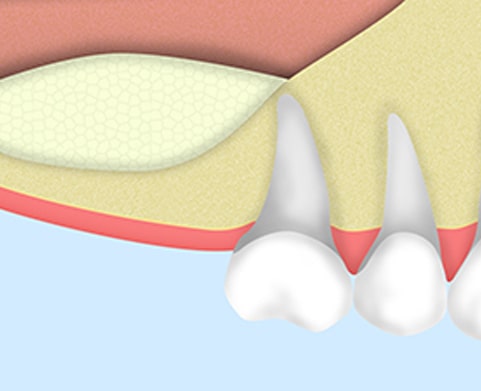

ソケットリフト

ソケットリフトはインプラント体を埋入するための骨の土台が薄い場合に、補填材等で骨を強化する治療法です。インプラント治療をするには骨が足りない場合にソケットリフト治療をおすすめしています。

ソケットリフトの進め方

骨が薄いままインプラントを埋めると、粘膜を傷つけ炎症を起こしてしまったり、インプラントが安定しない原因となります。

歯槽骨にドリルで穴を開けます。1mmの歯槽骨残した状態で、穴を掘るのを止めます。

ネジを入れた状態で3ヶ月待って、そのあとインプラントを入れていきます。